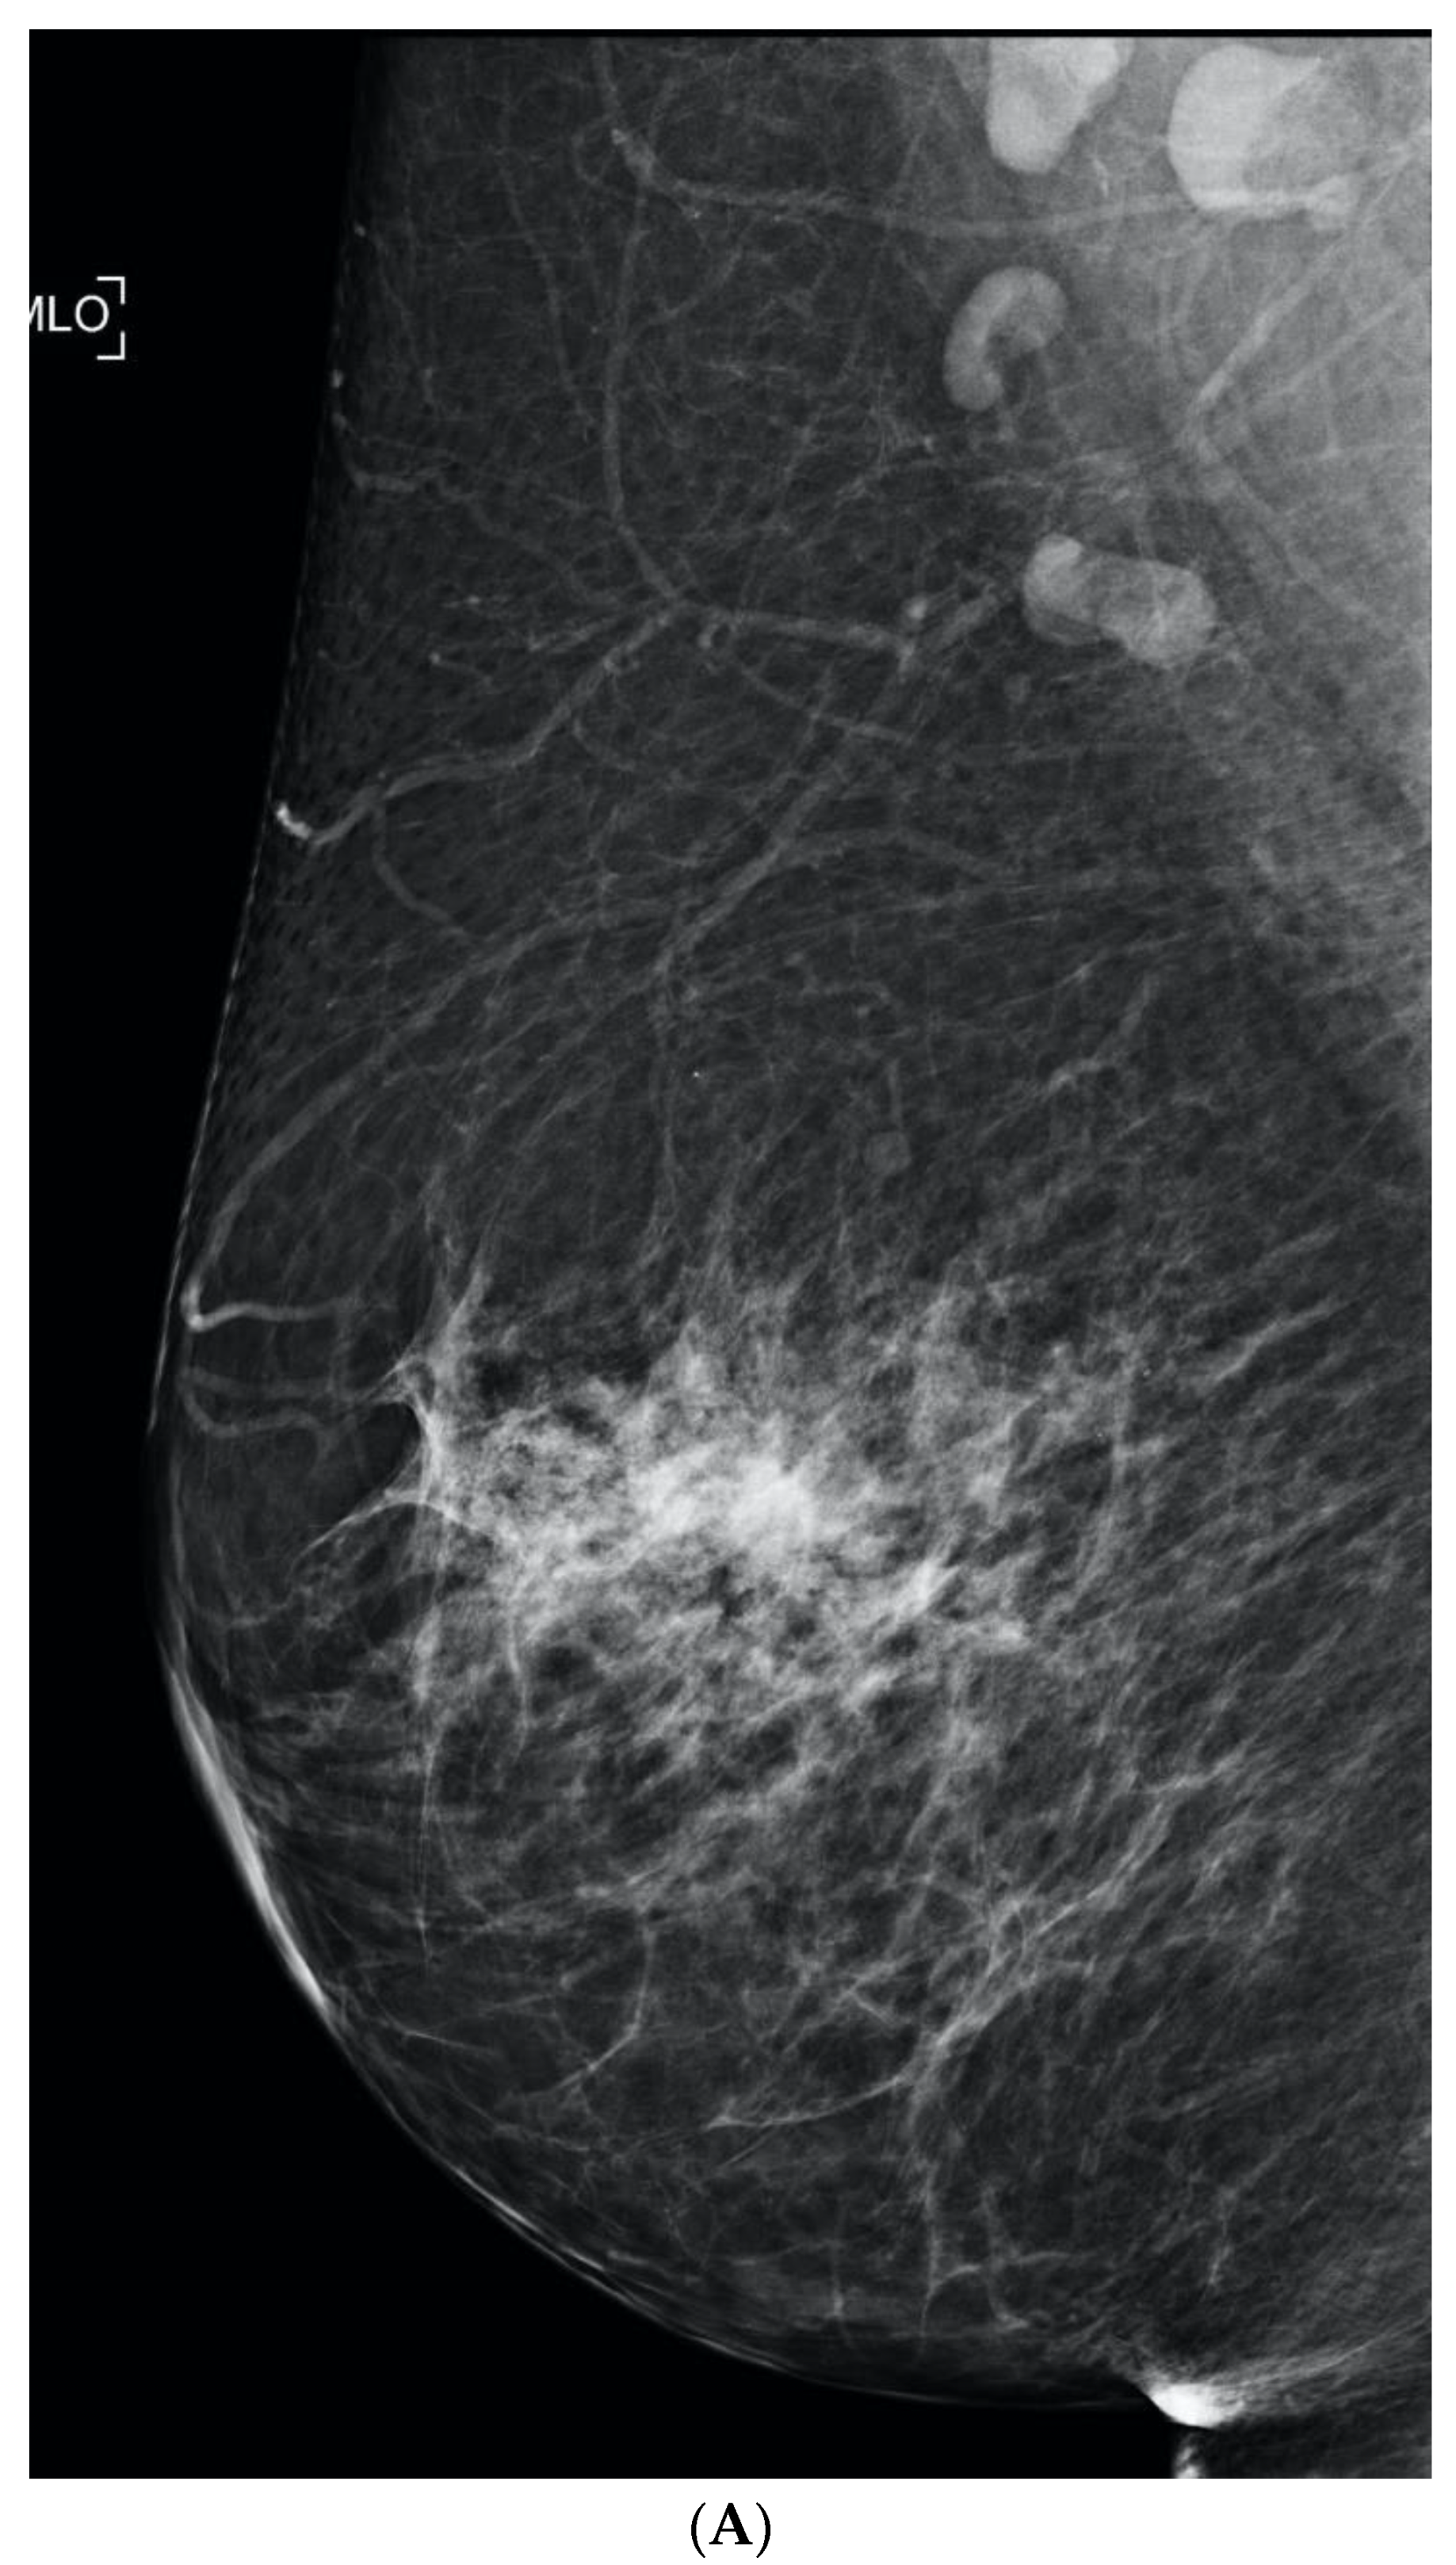

6. Digital Breast Tomosynthesis (DBT)